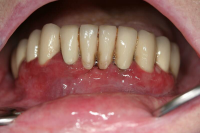

Gingival hälsa på intakt och reducerat parodontium.

Parodontal stabilitet karakteriseras av framgångsrik behandling genom kontroll av lokala och systemiska riskfaktorer, vilket resulterat i

- minimal blödning vid sondering (BVS < 10 % av tandytorna)

- fickdjup < 3 mm

- ingen progressiv parodontal nedbrytning/vävnadsförlust

- optimal förbättring i övriga kliniska parametrar hos behandlad parodontitpatient.